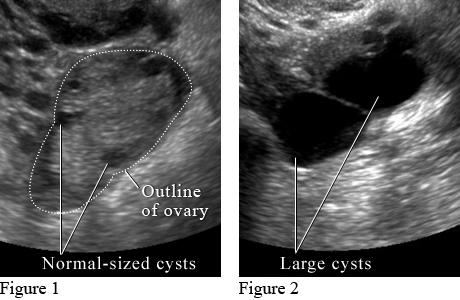

What do ovarian cysts look like on ultrasound?

Image courtesy of Intermountain Medical Imaging, Boise, Idaho.

Figure 1 shows small normal-sized cysts. Figure 2 shows large cysts that affect the ovary and may cause pain.